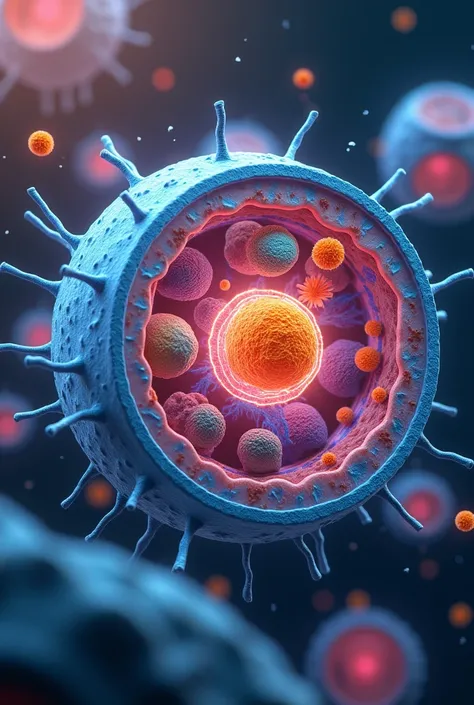

Pluripotent Hematopoietic Progenitor Cell

Pluripotent Hematopoietic Progenitor Cell

Pluripotent Hematopoietic Progenitor Cell

cell